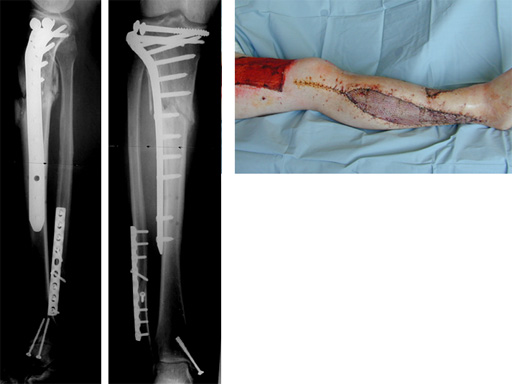

The LIS system for the proximal tibia is an anatomically pre-contoured implant for the treatment of fractures of the proximal tibia. In the course of a prospective clinical study, 135 patients with 138 fractures were treated with the new system at 13 European trauma centers from June 1998 to March 2000 and the cases were documented. The follow-up period was at least 12 months and ended in June 2001. Principle clinical investigator is C. Krettek, Hanover. AOCID monitored the study.

The inclusion criteria took in fractures of all degrees of severity of the proximal tibia and the tibial shaft. The fractures were classified as 110 fractures of the proximal tibia (AO 41) and 28 tibial shaft fractures (AO 42) according to the AO fracture classification system; type C fractures accounted for a total of 66% (n=91). A follow-up rate of 94% was achieved with reference to the number of fractures treated. The results of the study were evaluated immediately in close collaboration with the Principal Clinical Investigator. It is expected that the evaluation will be completed by the end of 2001; the results will be summarized and published in a final report.